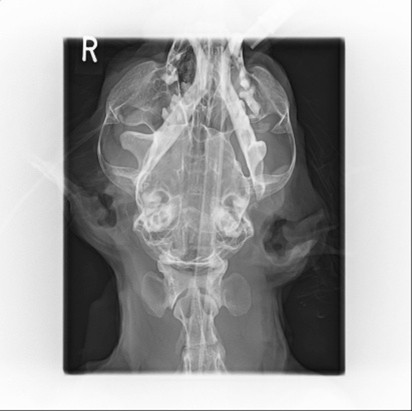

・レントゲン検査

診断を確定するために行います。頭部のレントゲンを撮影し、顎の関節が正常な位置からどれくらい、どちらの方向にずれているかを正確に確認します。また、顎の骨折など、他の重大な損傷がないかを調べる上でも非常に重要です。

診察時、下顎が前方に脱臼し、口が閉じられない状態でした。レントゲン画像を見ても、明らかに顎がずれていることがわかります。

飼い主様は、繰り返す脱臼に不安を感じておられました。当院では、再発を防ぐために、麻酔下で確実に整復する方針をご提案しました。全身麻酔をかけ、鉛筆を奥歯に噛ませて支点とし、テコの原理を利用して慎重かつ大胆に下顎を元の位置へ整復しました。